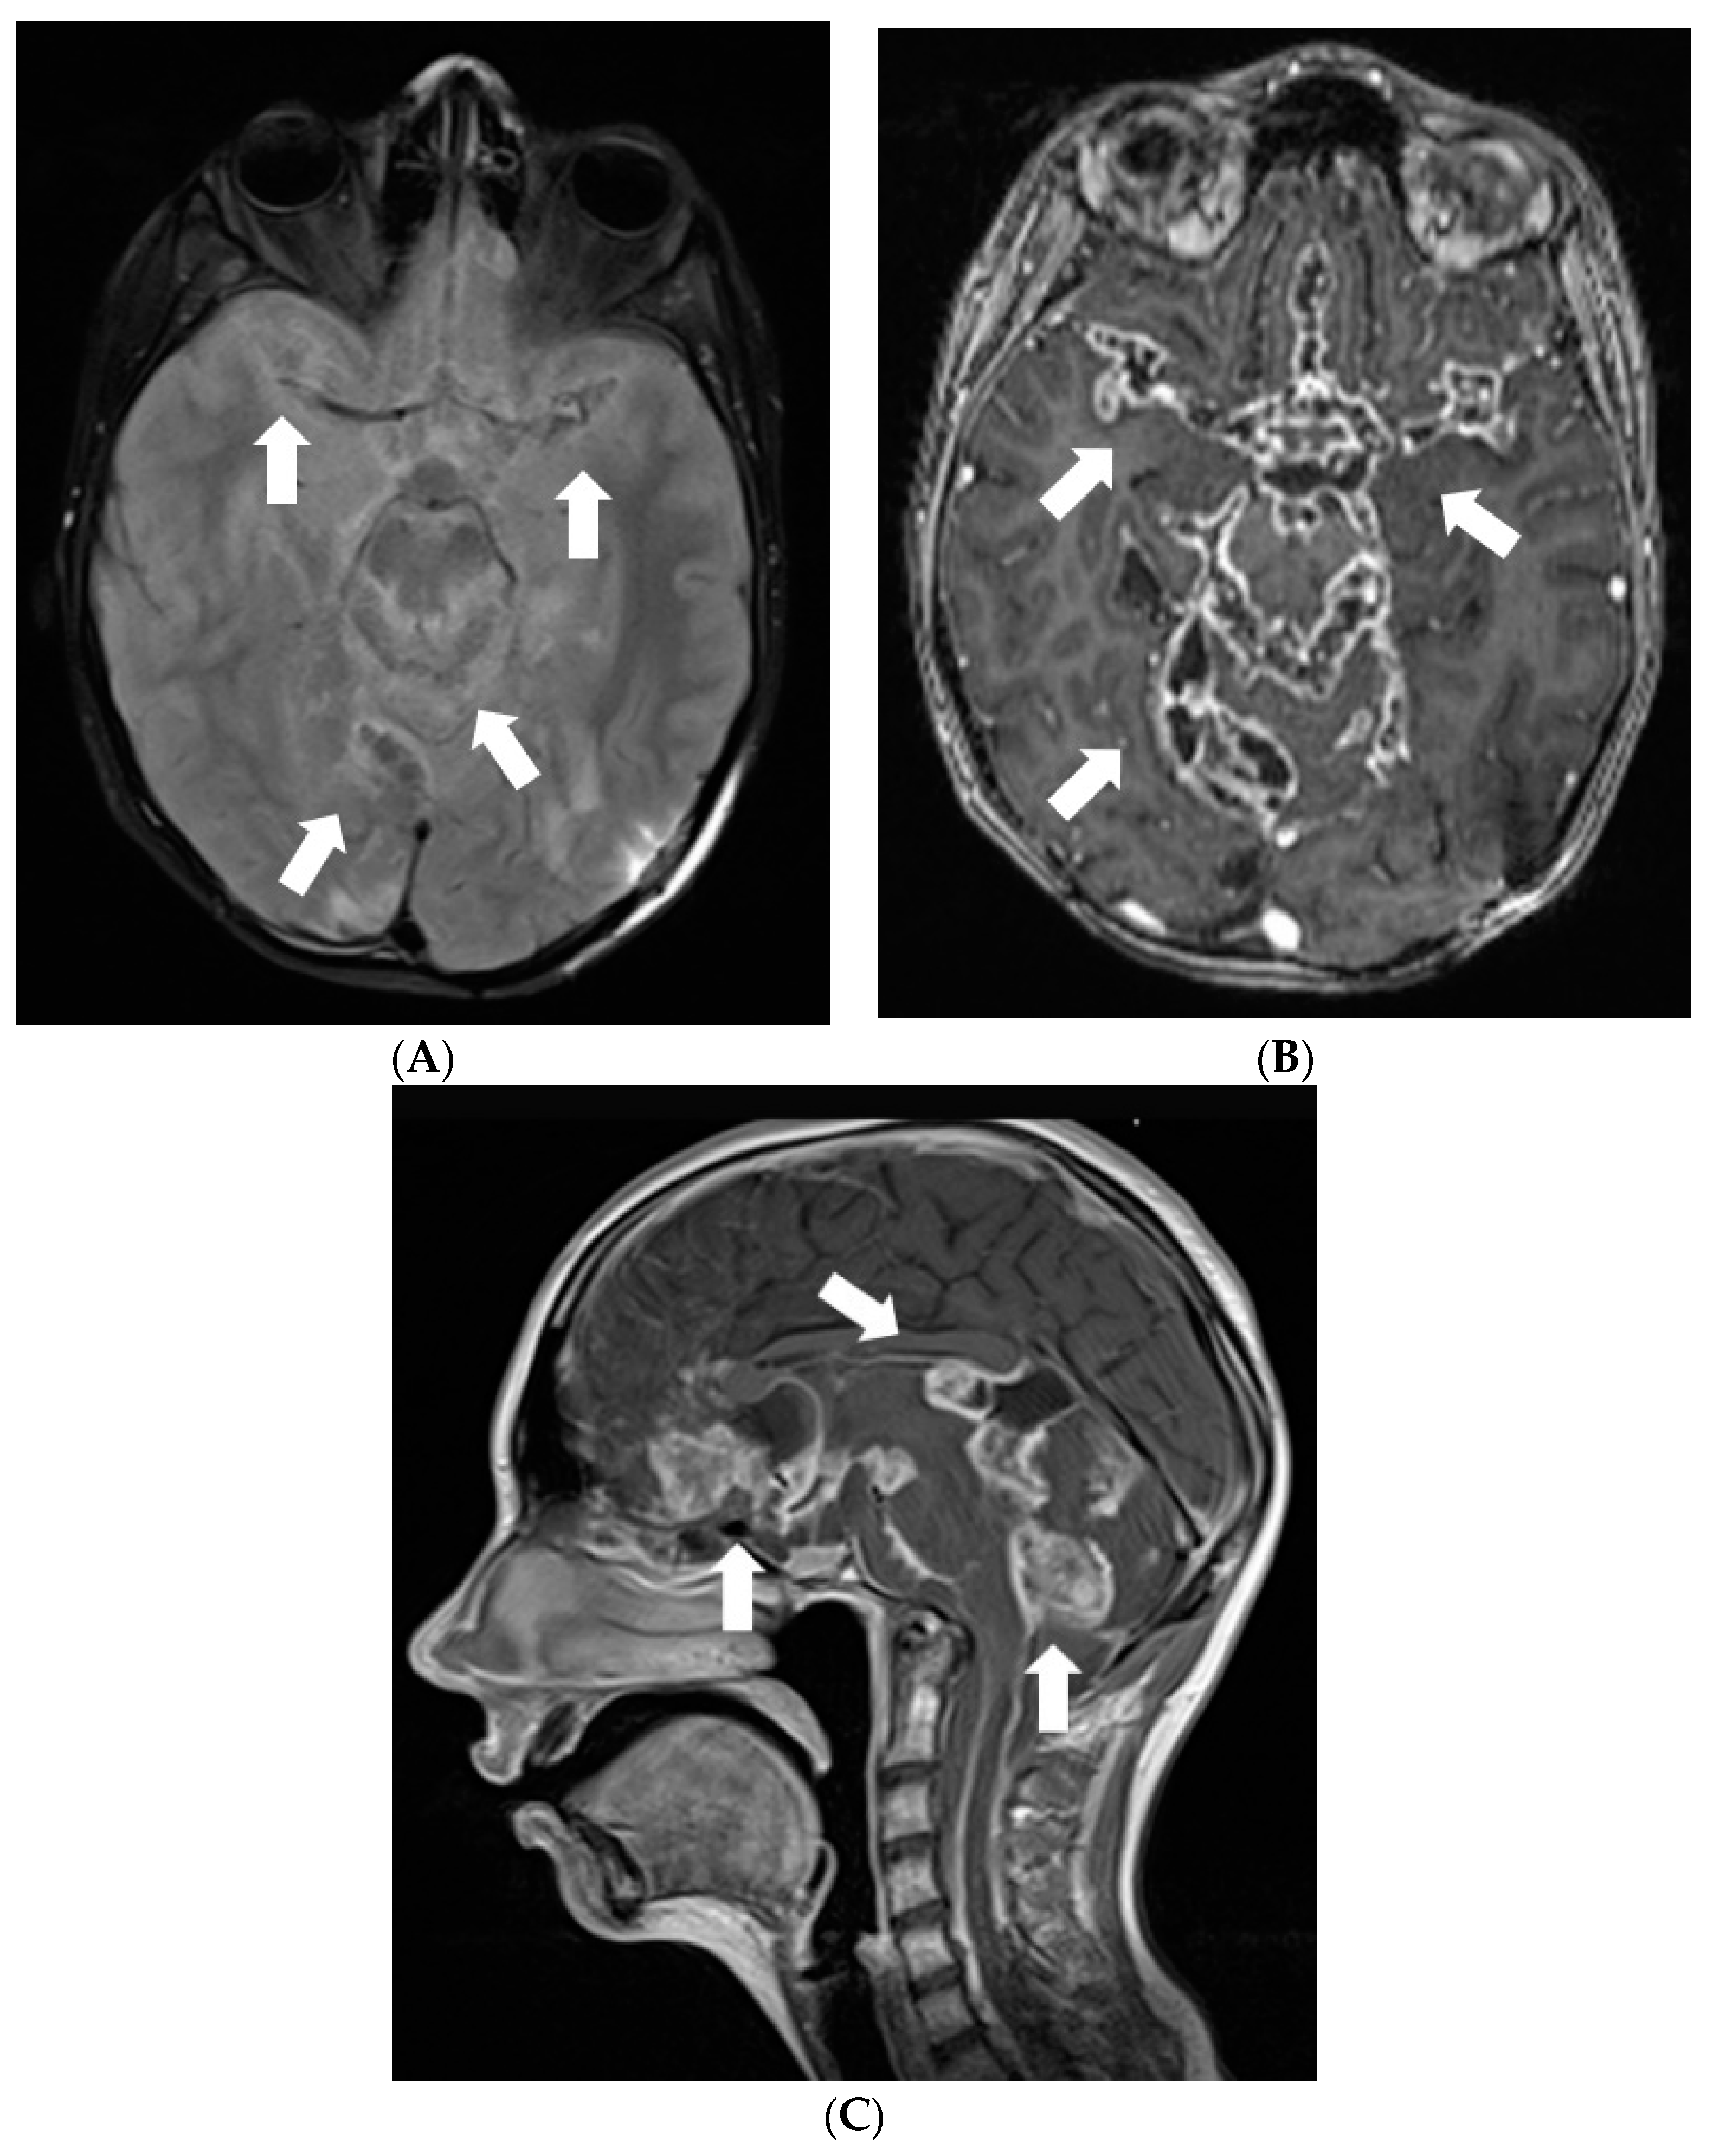

After 4 months when symptoms of raised intracranial pressure recurred, additional findings were detected on follow-up MRI. Most of the subarachnoid cisterns, Sylvian fissures, sulci of superior parts of the cerebellum, and the lower part of the fourth ventricle were filled with diffuse non-contrast-enhancing multiple small cyst-like lesions (Figure 3). These lesions were more evident on T2W/FLAIR and T2W/SPC images; T2W/FLAIR revealed iso/slightly hypointense lesions resembling cysts in the previously mentioned areas. The lesions did not show diffusion restriction or any significant compression of adjacent structures. Additionally, magnetic resonance spectroscopy of the lesion demonstrated lactate peak. Due to the uncertain origin of the findings, a biopsy of the newly detected tissue in the perimesencephalic cistern was performed. Histological appearance and immunohistochemical phenotype of the sample were the same as in the previous examination, consistent with subarachnoid spread.

Figure 3.

Follow-up MRI of the brain 1 year after the onset of the symptoms (April 2012): (A) Axial T2W/FLAIR/FS and (B) T2W/SPC images disclose masses composed of multiple small cysts in the subarachnoid cisterns, Sylvian fissures, and cerebellar sulci. There is no contrast enhancement (C) in the referred areas.

Later the girl was treated in Klaipeda University Hospital. In May 2013, a follow-up MRI demonstrated enlarged cystic lesions in the subarachnoid spaces with compression of the brainstem and the cerebellum and vivid leptomeningeal enhancement extending to the spinal canal (Figure 4). T2W/FLAIR/FS images revealed heterogenous, slightly hyperintense lesions with hypointense foci in the subarachnoid spaces. Clinically, ataxia and weakness of the legs worsened. Partial resection of the neoplastic masses from premedullary cisterns and the IVth ventricle was performed. It was decided to administer chemotherapy with temozolomide. Gradually, the condition of the patient improved.

Figure 4.

Follow-up MRI of the brain 2 years after the onset of symptoms (May 2013): (A) Axial T2W/FLAIR/FS, (B) axial, and (C) sagittal T1W postcontrast images demonstrate enlarged cystic lesions in the subarachnoid spaces causing compression of the brainstem and the fourth ventricle and vivid leptomeningeal enhancement extending to the spinal canal.